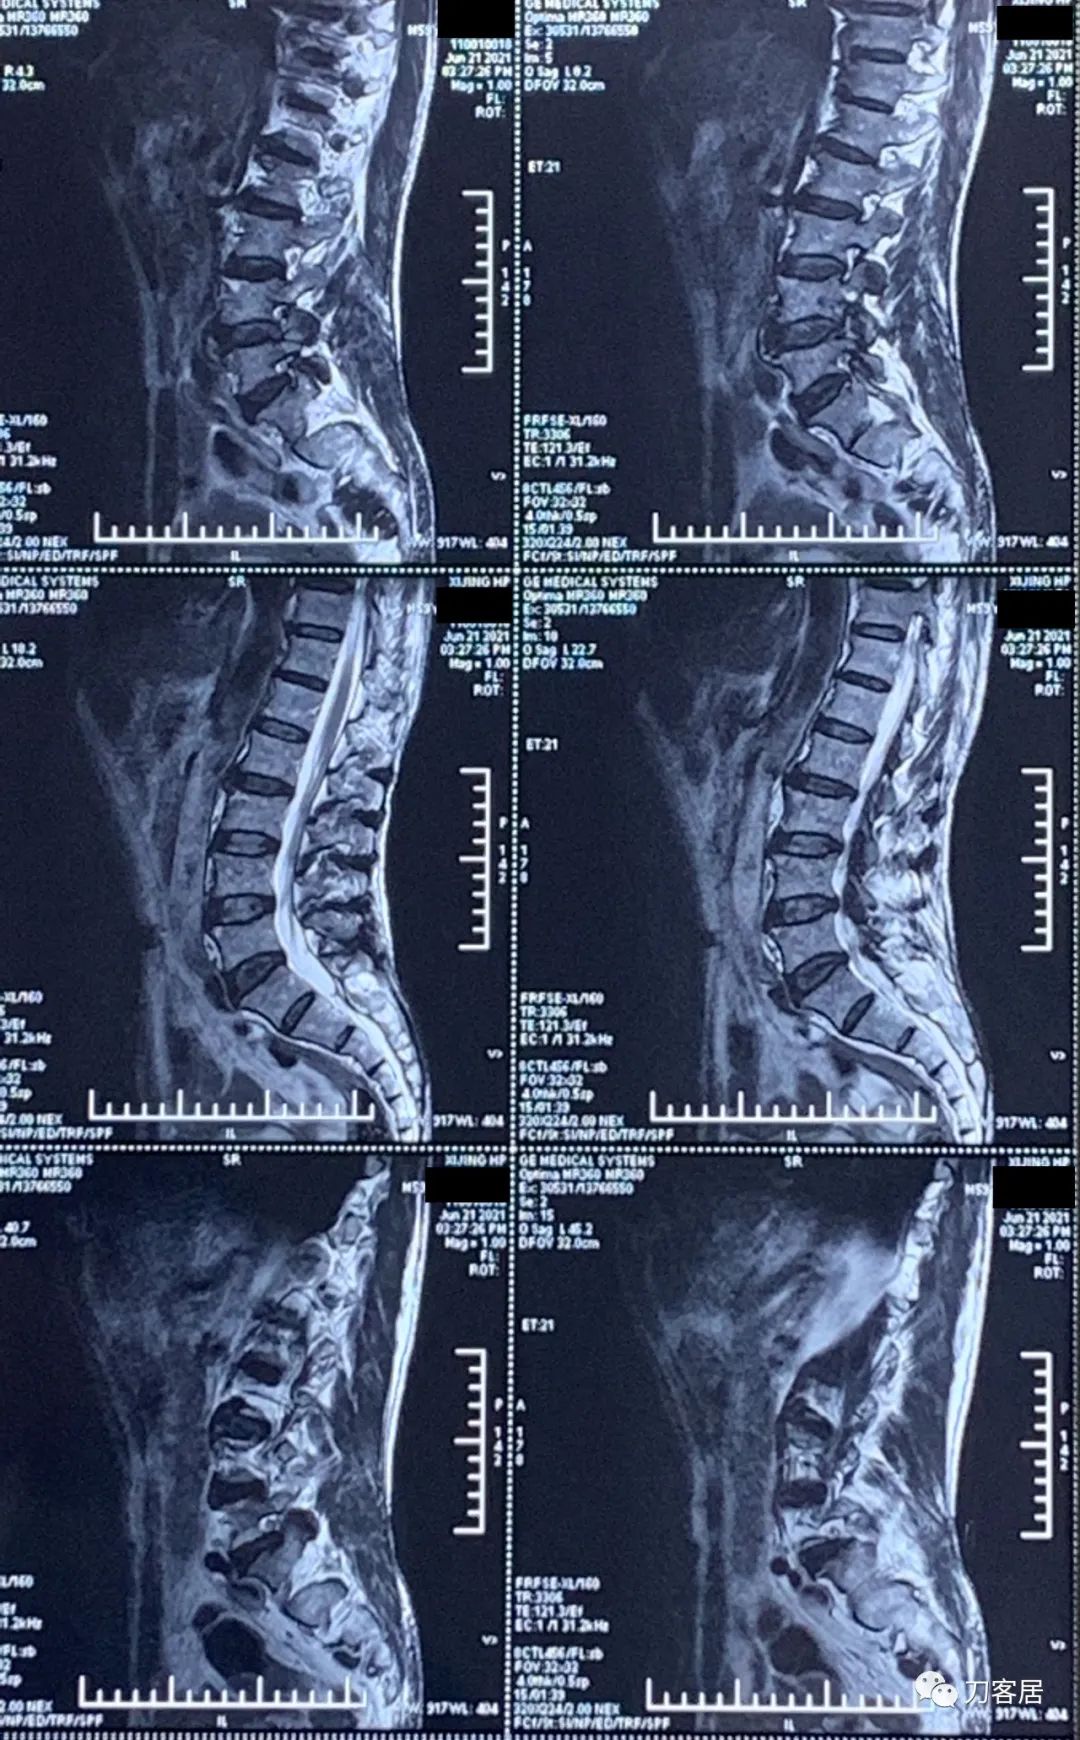

图3. 20210621西京医院腰椎MRI01

图4. 20210621西京医院腰椎MRI02

图5. 20210621西京医院腰椎MRI03

图6. 20210621西京医院腰椎MRI04

图7. 20210621西京医院腰椎MRI05